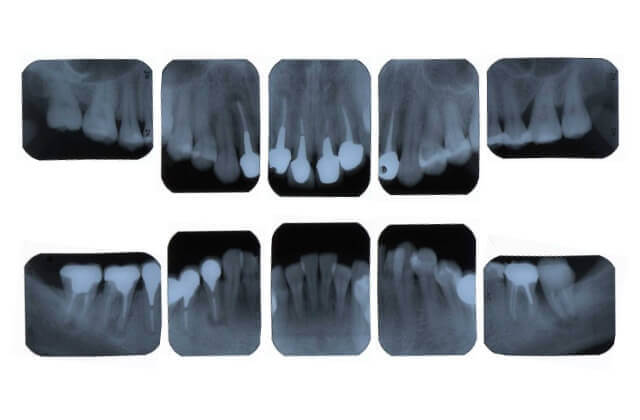

デンタル10枚法

細かくレントゲン写真を撮影することにより虫歯、歯根・歯槽骨の状態などをしらべます